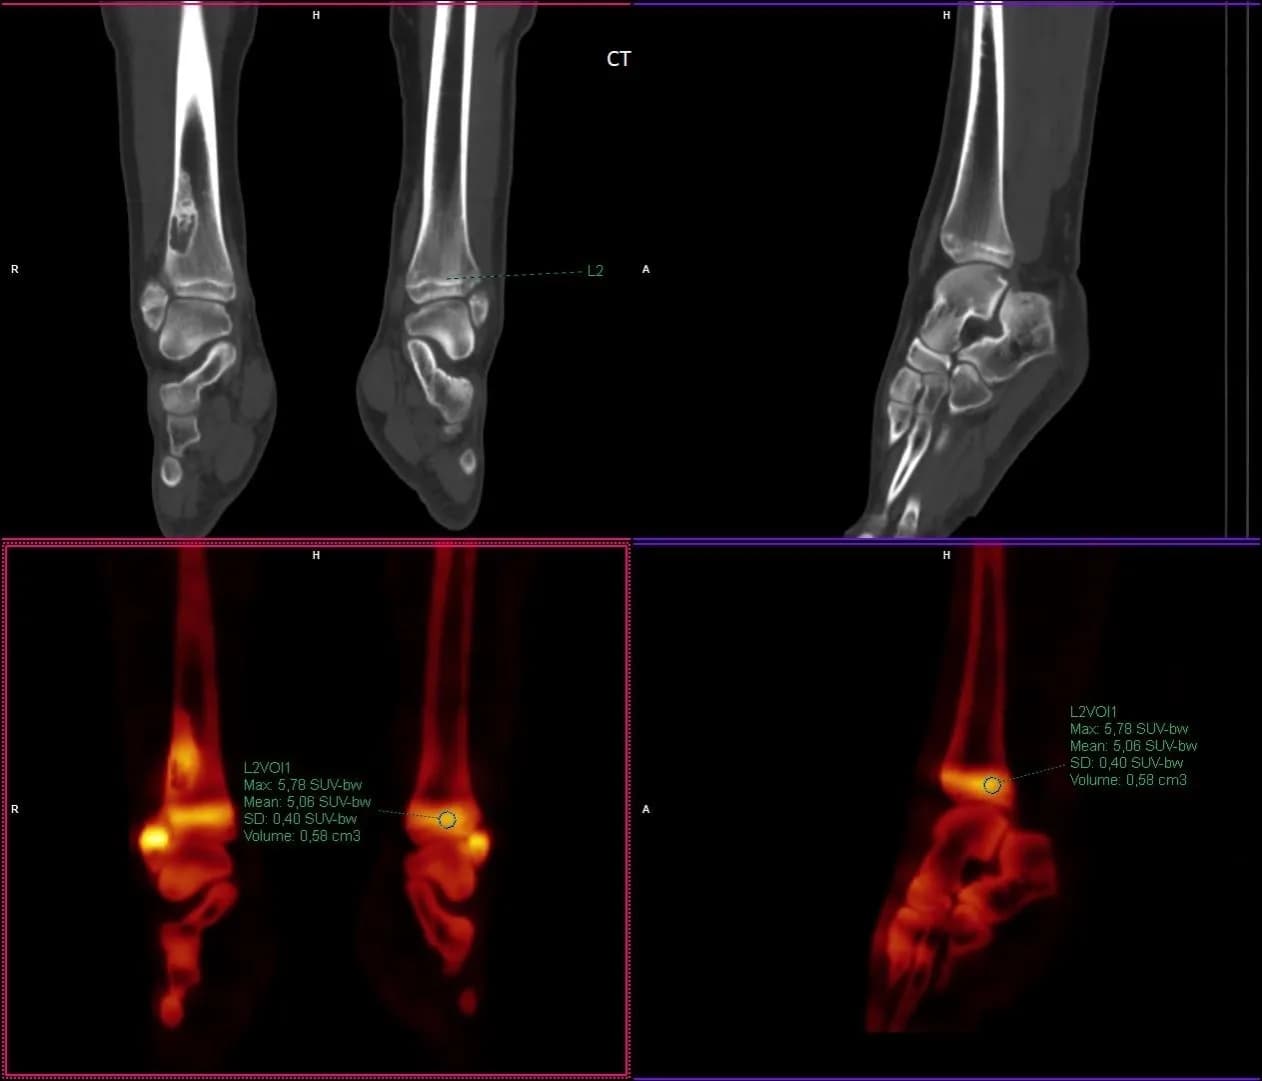

Co to jest SUV max i dlaczego jest kluczowy w diagnostyce?

Dowiedz się, co to jest SUVmax i jak ten wskaźnik wpływa na diagnostykę nowotworów oraz decyzje terapeutyczne w onkologii.